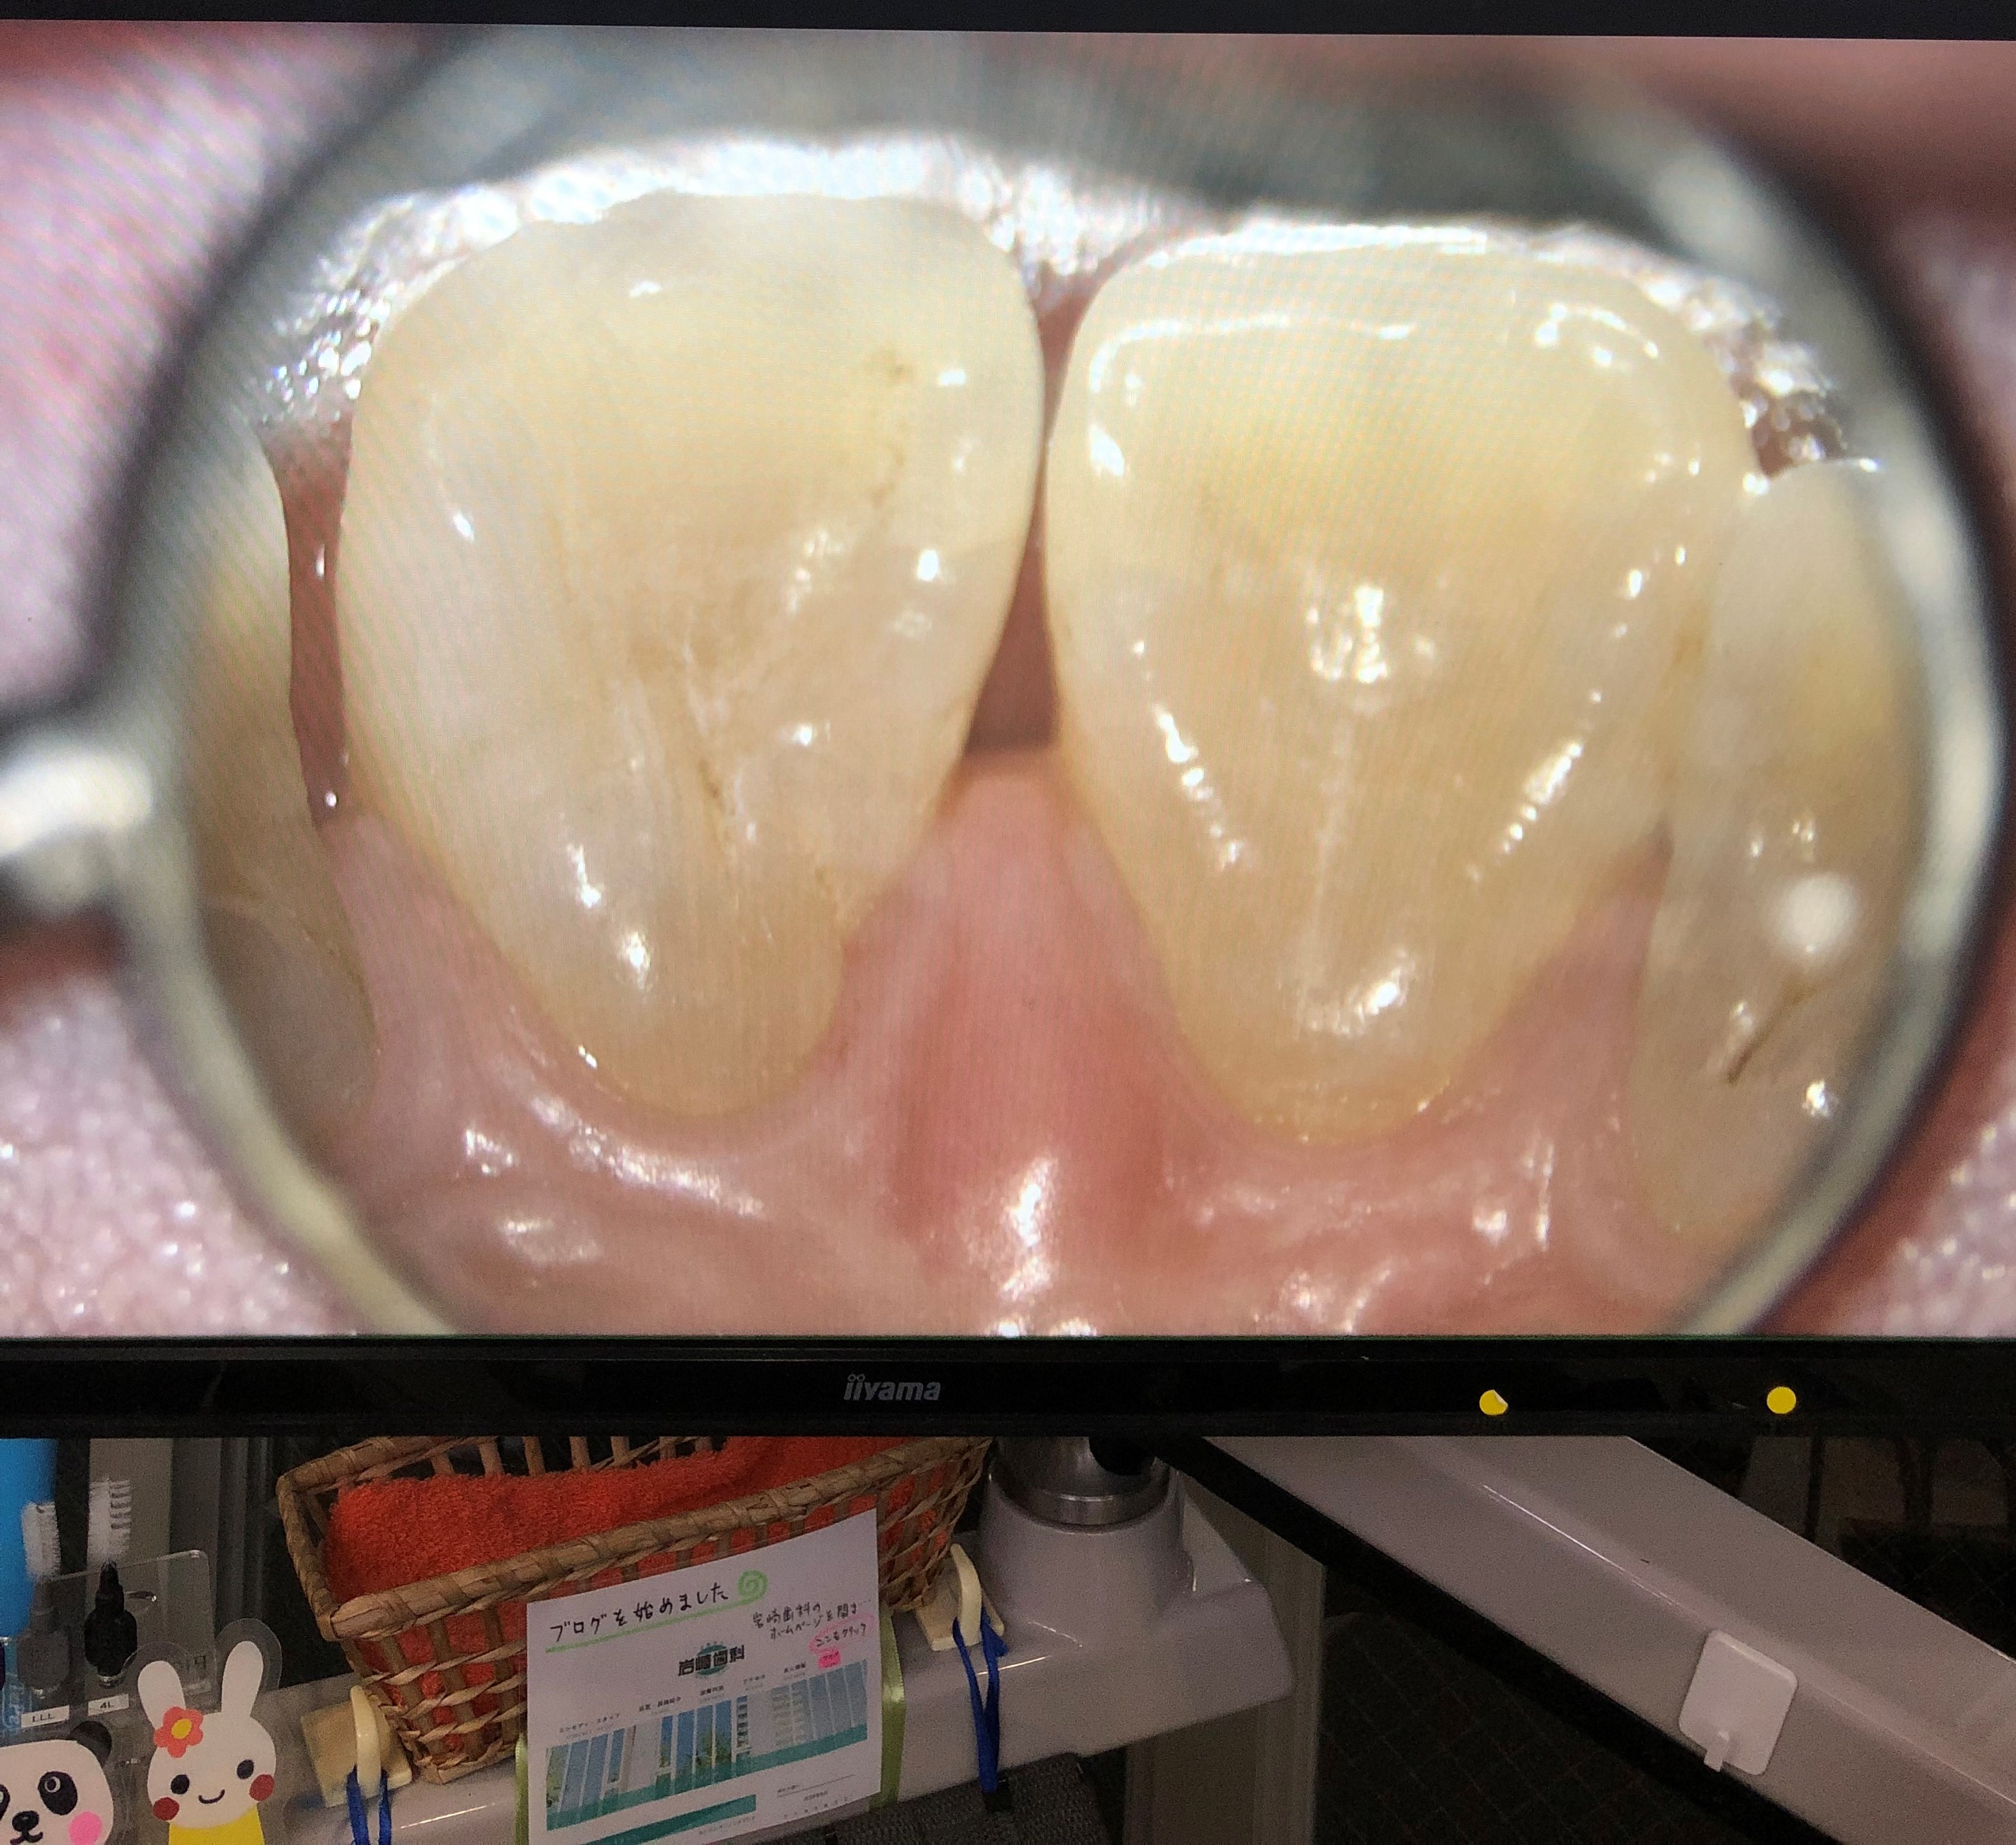

審美歯科内容

審美歯科治療とは、天然歯のように自然で美しい口元を作ることを目的とした治療です。しかしながら、見た目の美しさの回復は、歯や歯茎の健康はもちろん、咬み合わせなどの正常な機能を持続させることにも貢献しています。主な治療として、歯を削らないホワイトニング、セラミッククラウン・インレーによる修復治療と、表面だけを削るラミネートベニヤなどがあります。様々な目的・処置方法がございますので、審美歯科治療にかかる治療費は、治療法により大きく異なります。失った歯の代わりに人工歯根(インプラント)を埋め込み、その上に人工の歯を装着します。健康な歯を削ることはありません。